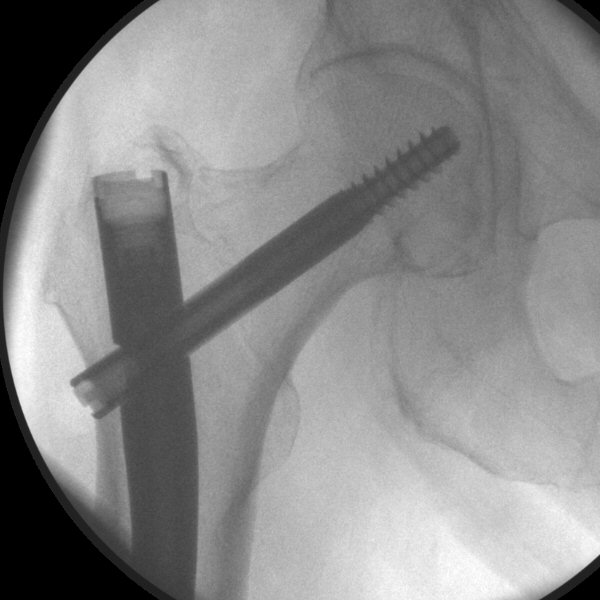

- För in låsskruvsguiden ända in till benet, tryck hårt så den går igenom fascian, lås fast genom att skruva på "Target Sleeve Knob", borra i genomlysning, tryck först mycket försiktigt mot första kortex så borret gör ett märke i kortex, sedan kan man trycka hårdare. Borra igenom båda kortex, borren ska inte träffa spiken.

- Mät med mätsticka hur lång skruv som behövs, avrunda uppåt.

- Skruva in låsskruven, kontrollera läget med genomlysning, den ska gå genom båda kortex.